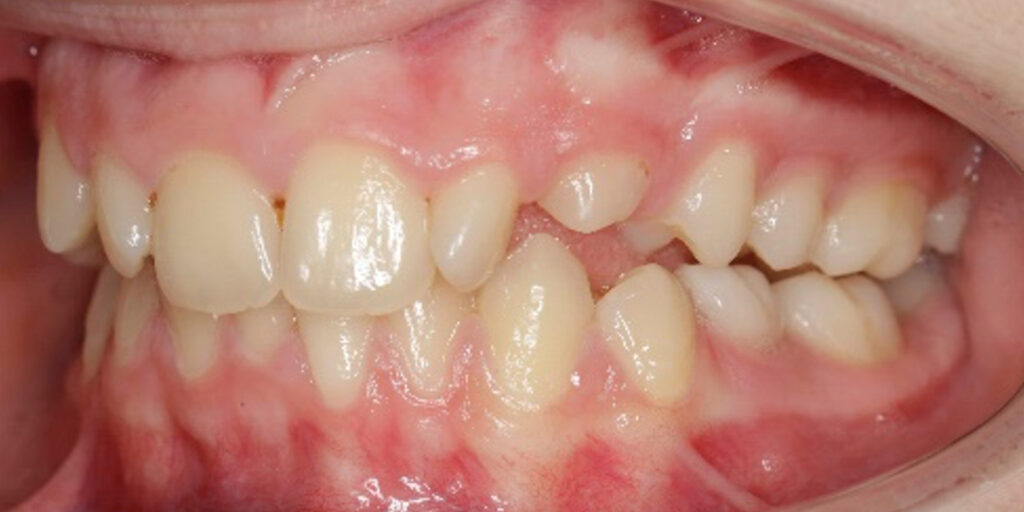

BEFORE

Diagnosis

The 14-year-old female patient visited the orthodontic practice in February 2021. The chief complaint was that her upper arch was affecting her confidence in her smile. Upon examination, the patient was found to have a normodivergent facial pattern and a skeletal class II with mandibular retrusion. An intraoral examination revealed narrow arches, a class II molar and canine relationship, deep bite, retroclined upper and lower incisors, and retained teeth 63, 74, and 84.